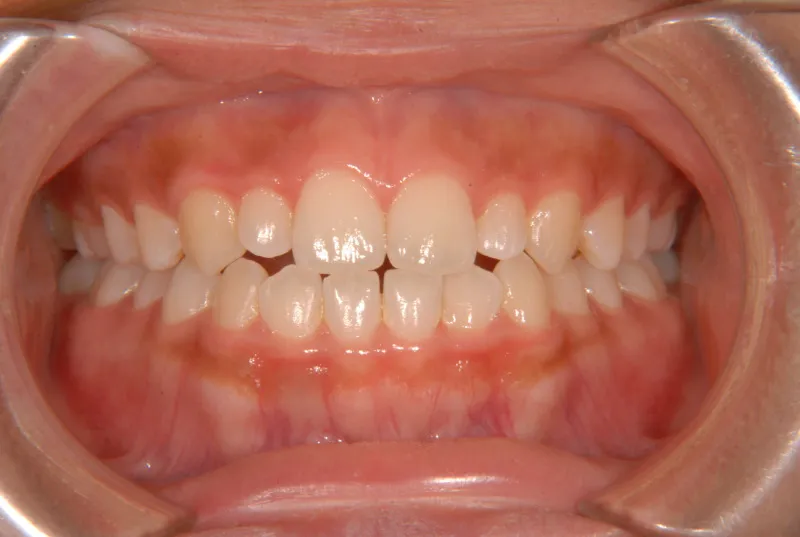

開咬・舌癖・18歳女性

初診時年齢 高校生 (女性) 主訴 開咬 舌癖

状態 前歯で噛めない(開咬/オープンバイト)